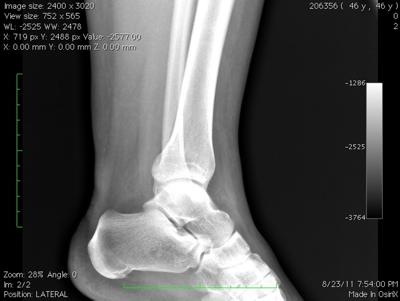

Whilst I look at lots of X-rays I'm not a trained radiologist, and thus I'm reluctant to give an opinion, particularly seeing that I can't examine your foot itself.

It does seem there is some swelling adjacent to the lateral malleolus, but I can't see any fracture. This is probably due to some sprain of the ligaments.

The posterior process of the talus seems somewhat enlarged, but has nothing to do with the injury. However, it would limit movement in the subtalar joint.